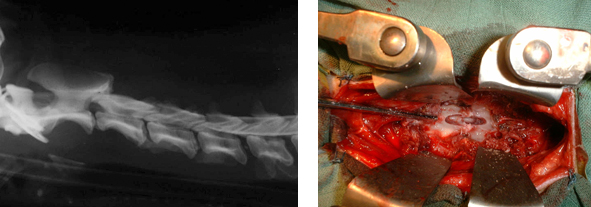

Stabilisation du rachis cervical par vis verrouillées et plaques intersomatiques en titane.

Après corpectomie, la récupération est normalement très rapide. L'intervention est cependant délicate : des risques de saignements abondants sont possibles en cas de lésions vasculaires.

Laminectomie et Hémilaminectomie.

Après anesthésie générale, l'animal est disposé en décubitus ventral.

Le principe est d'aborder le rachis par voie dorsale ou dorsolatérale. Une partie (hémilaminectomie) ou la totalité (laminectomie) de la lame dorsale de la vertèbre est retirée au moyen d'une fraise neurochirurgicale et de rongeurs spéciaux. Il est ainsi pratiqué une fenêtre dans la vertèbre qui permet, à la fois de décomprimer le tissu nerveux, et d'accéder au matériel discal hernié qui peut être retiré.